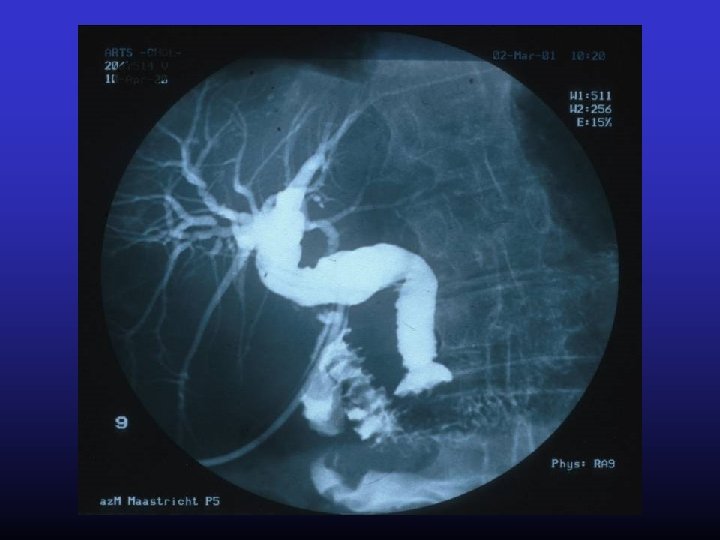

Intraoperatie cholangiogram • Mirizzi PL (1893 -1964) • La cholangiographia durante las operaciones de las vias biliares • Bol Soc Cir Buenos Aires, 1932; 16: 11331135

Reden voor intra-operatief cholangiogram • Verdenking stenen in CBD • Onduidelijke anatomie • Vermijden CBD letsel

Intra-operatief cholangiogram • Op indicatie – CBD dilatatie – Anatomie – Sterke verdenking steen in CBD